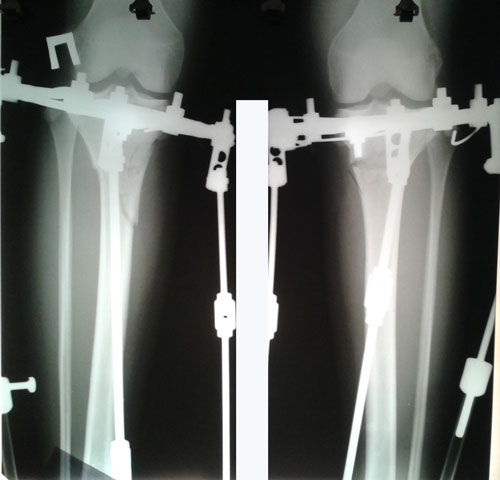

РЕНТГЕН ДО ОПЕРАЦИИ

Рентген в процессе коррекции